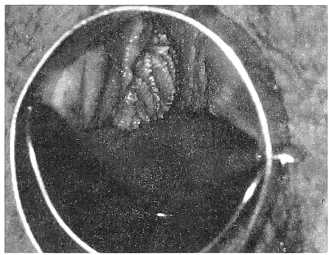

Обширные экзофитные кондиломы в области входа во влагалище представлены на рис. 4, 5. В первом случае (рис. 4) макроскопически видны кондиломатозные разрастания в области задней спайки с переходом на слизистую малых половых губ, больше справа.

Рис. 4. Кондиломатозные разрастания в виде «цветной капусты» в области задней спайки

Эти разрастания имеют вид выступающих бархатистых «белых полей«. Во втором случае (рис. 5) — множественные кондиломы в виде «бородавок», закрывающие вход во влагалище.